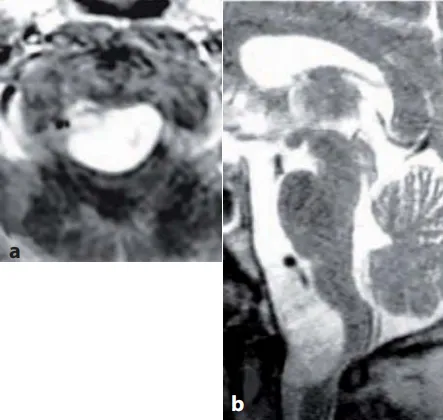

脑膜瘤属于常见良性肿瘤类型,通常进展缓慢,手术后预后良好。颅颈交界区脑膜瘤在所有脑膜瘤中占比1.8%-3.2%,其中约70%的颅颈交界区肿瘤为良性脑膜瘤。此类肿瘤确诊时体积通常较大,手术主要目标为实现肿瘤完全切除。但由于该区域解剖结构复杂,肿瘤与重要血管、脑干及颅神经关系密切,完全切除难度较高。成功完成该区域手术需要丰富的脊柱和颅底解剖学知识经验,同时需兼顾神经功能保护与头颈部生物力学重建。

颅颈交界区涵盖枕骨大孔(含枕髁)、寰椎、枢椎及其相关韧带关节,包含椎动脉、延髓脊髓和后组颅神经等重要结构,具有生物力学复杂和功能重要等特点。

手术目标需根据病变特点个体化制定。虽然脑膜瘤全切是理想目标,但需权衡并发症风险。术前评估应包含三平面MRI、血管造影、CT血管造影三维重建等影像学检查,结合解剖变异和临床表现制定个性化方案。